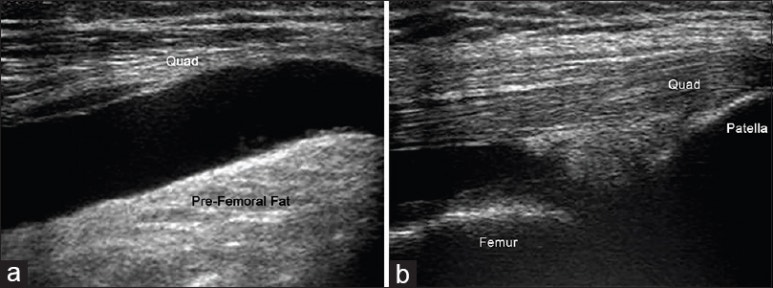

출처: Carlos Frederico Arend,Sonography of the iliotibial band: spectrum of findings 위 초음파 이미지에서

빨간 화살표가

장경인대인데요.

딱 붙어있다던

노란색 화살표

대퇴골 외상과와

부딪히면서

염증이 생기게 됩니다.

위 초음파 소견처럼

관절 안에 염증으로

물이 차서

부어있는 환자들이

있는데요.